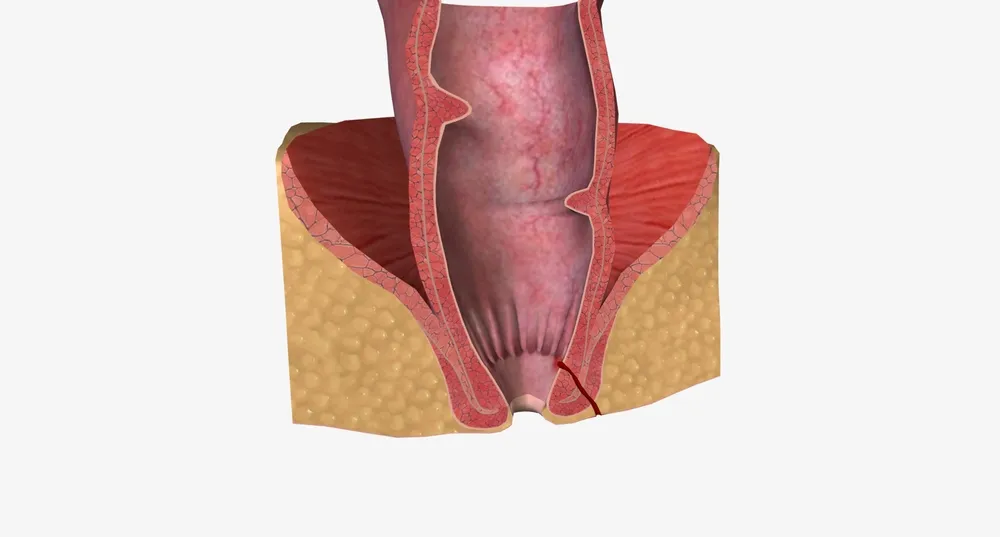

شقاق مقعد و ایجاد زخمهای دردناک

شقاق مقعد یا ترک خوردگی دیواره مقعد یکی از مشکلات شایع ناحیه نشیمنگاه است که باعث درد شدید و ناراحتی هنگام دفع میشود. این زخمها معمولاً به شکل خطی و کوچک در پوست یا مخاط اطراف مقعد ظاهر میشوند و با خونریزی سطحی، سوزش و التهاب همراه می باشند.

علل شقاق مقعد

یبوست مزمن و زور زدن هنگام دفع: فشار بیش از حد باعث ترک خوردن پوست حساس مقعد میشود.

اسهال مزمن: حرکات مکرر روده و تماس مداوم با مدفوع اسیدی موجب تحریک و ایجاد زخم میشود.

زایمان یا آسیب فیزیکی: فشار مستقیم و آسیب به ناحیه مقعد در برخی شرایط باعث شقاق میشود.

رژیم غذایی کم فیبر: مصرف ناکافی فیبر باعث سفت شدن مدفوع و افزایش احتمال ترک خوردگی میشود.

علائم شقاق

شقاق مقعد با درد شدید هنگام دفع، خونریزی سطحی و التهاب موضعی مشخص میشود. در برخی موارد، این درد تا چند ساعت پس از دفع ادامه پیدا میکند و کیفیت زندگی فرد را تحت تأثیر قرار میدهد.

اهمیت درمان به موقع

عدم درمان شقاق منجر به مزمن شدن زخم، ایجاد اسپاسم عضله مقعد و عفونتهای ثانویه می شود. درمان شامل تغییر سبک زندگی، مصرف ملینها، داروهای موضعی و در موارد شدید جراحی جزئی است.